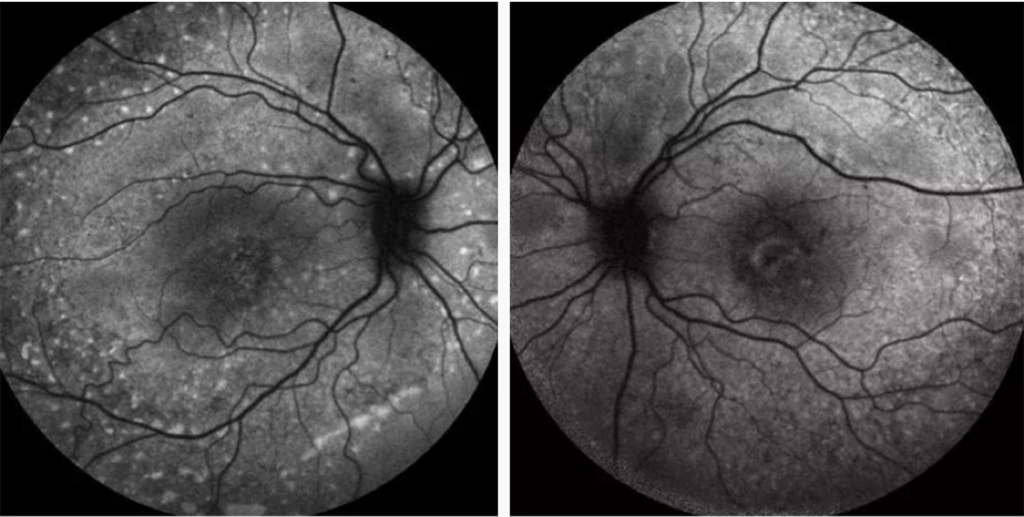

Autofluorescência do fundo ocular

A autofluorescência do fundo de olho é uma técnica de imagem importante para o diagnóstico e o monitoramento da DMRI, particularmente de uma de suas formas avançadas, a atrofia geográfica.1 Quando exposta a uma luz específica (normalmente azul), uma molécula no olho chamada lipofuscina produz luz, ou fluorescência, que pode ser observada. Regiões não saudáveis podem parecer mais escuras para áreas atróficas, ou mais brilhantes para drusas, que são sinais de DMRI.7